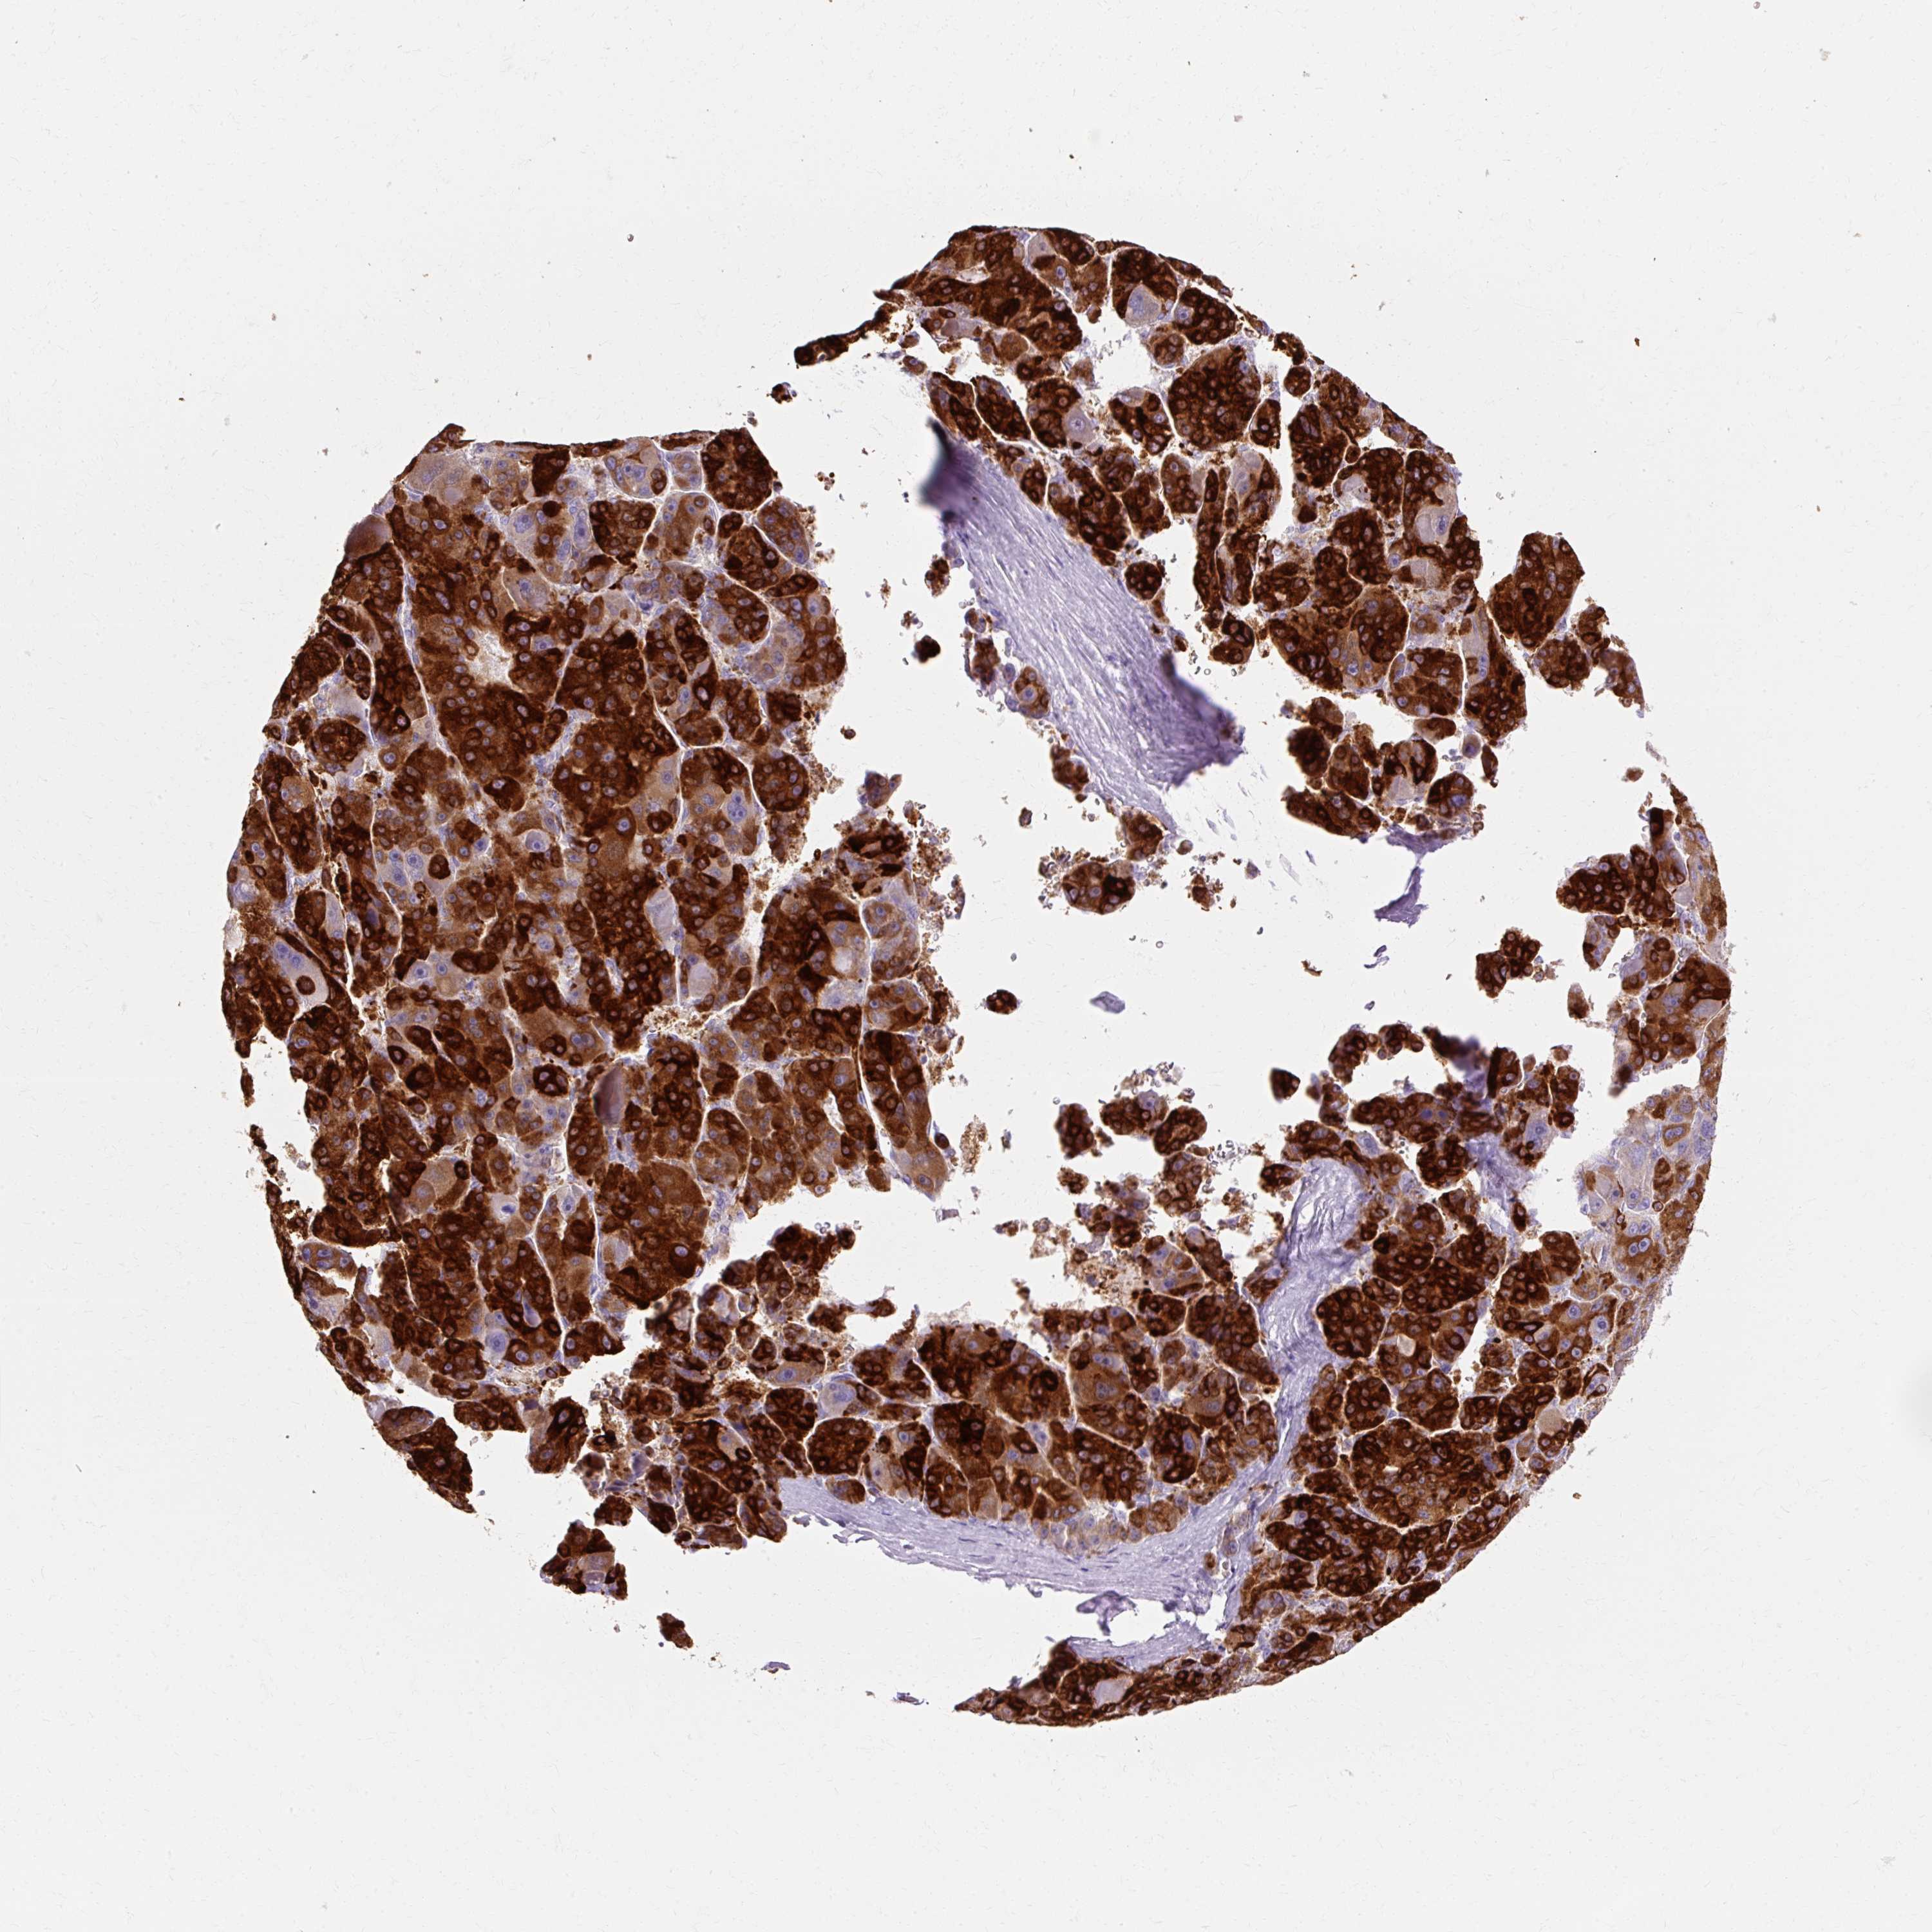

LIVER CANCER - Protein expressioni

A mouse-over function shows sample information and annotation data. Click on an image to view it in a full screen mode. Samples can be filtered based on level of antibody staining by selecting one or several of the following categories: high, medium, low and not detected. The assay and annotation is described here.

Antibody stainingi

Antibody staining in the annotated cell types in the current human tissue is reported as not detected, low, medium, or high, based on conventional immunohistochemistry profiling in selected tissues. This score is based on the combination of the staining intensity and fraction of stained cells.

Each image is clickable and will lead to virtual microscopy that enables deeper exploration of all samples and also displays staining intensity scores, fraction scores and subcellular localization as well as patient and tissue information for each sample.

Antibody HPA047729

Staining

High

Medium

Low

Not detected

Intensity

Strong

Moderate

Weak

Negative

Quantity

>75%

75%-25%

<25%

None

Location

Nuclear

Cytoplasmic/membranous

Cytoplasmic/membranous,nuclear

Cholangiocarcinoma

Carcinoma, Hepatocellular, NOS